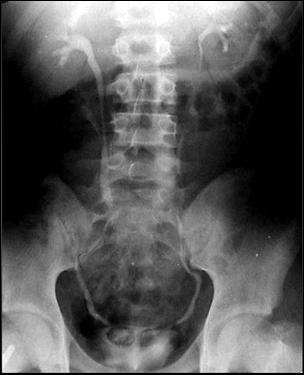

Diagnosticul diferential cu tuberculoza urogenitala

Vezica urinara are contururi greu delimitabile pe cistografie si pacientul are ureterohidronefroza bilaterala.

|

Figura 57. Vezica urinara mica |

Vezica urinara mica, scleroasa, cu rinichi drept unic chirurgical, uretero-hidronefroza gr I